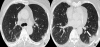

Case presentation: Here, we describe a rare case of acute fibrinous and organising pneumonia, in an otherwise healthy 65-year-old Greek woman who complained of dry cough, fever, weight loss and progressive dyspnoea. She had never been a smoker. Her clinical symptoms showed a rapid deterioration in the two weeks before admission, despite a course of oral antibiotics. After excluding infection and malignancy with routine laboratory tests and flexible bronchoscopy, high resolution computed tomography and video assisted thoracoscopic lung biopsy were performed. Diagnosis was based on radiological features typical of community organising pneumonia coupled with pathologic features characteristic of acute fibrinous and organising pneumonia. The patient was treated with corticosteroids and showed excellent clinical and radiological response three months after treatment initiation.